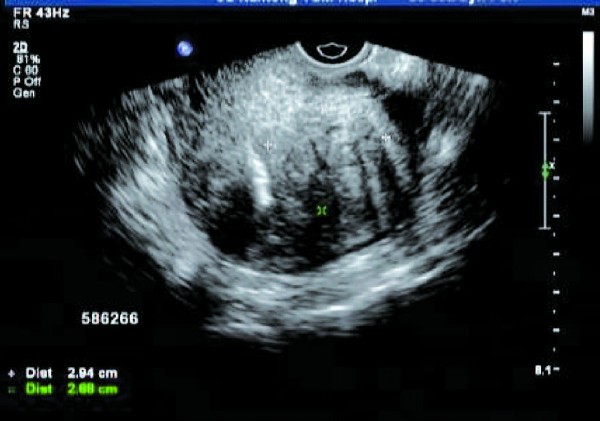

患者,女,47岁。常规体检,B超报告显示: 子宫体前位,大小: 4.63cm×3.97cm×3.78cm,宫颈长:2.56cm。宫壁回声不均匀,肌层回声呈粗颗粒状,外形平滑,后壁厚度2倍于前壁,内膜带状,规则,均质。双卵巢均可探及正常大小,位置正常,未见异常血流信号及频谱。宫旁未见明显占位,直肠窝无暗区。

超声提示:子宫后壁腺肌症